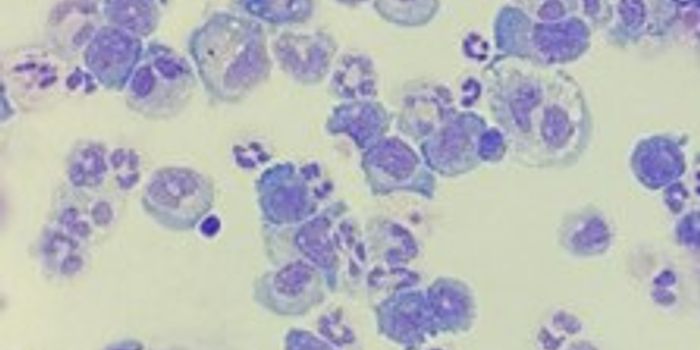

DEC 10, 2016ImmunologyFor high-risk cancer patients with acute myeloid leukemia (AML), oncologists are interested in supplementing bone marrow ...